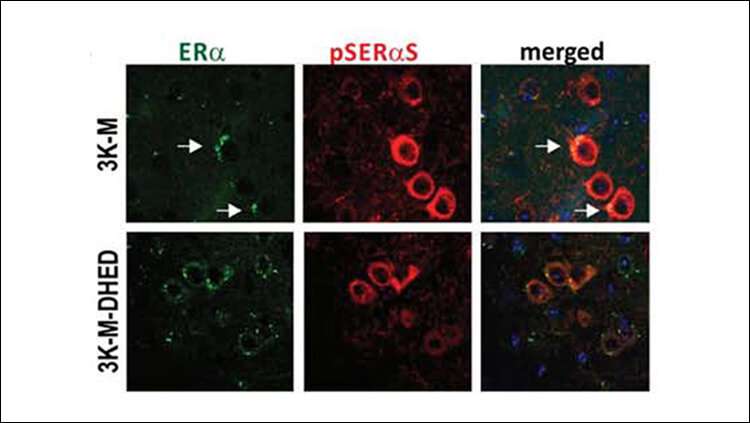

Immagine, microscopia confocale di neuroni nei topi di controllo (in alto) e trattati con estrogeni con patologia simile al Parkinson. Il trattamento con estrogeni provoca livelli più alti di estrogeni (verde) e riduce i sintomi del Parkinson. Credito: Rajsombath et al., JNeurosci 2019.